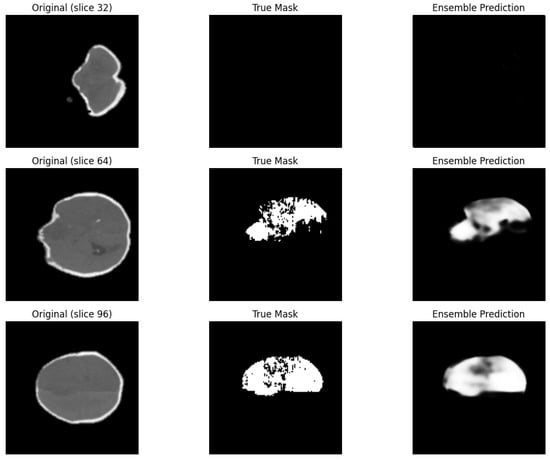

Figure 8 presents a comparison between ground-truth segmentation masks and the results obtained using the ensemble of the SE-UNETR and Swin UNETR models. For analysis, three representative slices from a volumetric brain CT scan were selected—the initial (slice 32), middle (slice 64), and final (slice 96)—allowing for an assessment of the model’s consistency across different scanning stages.

The first column shows the original CT slices, depicting the anatomical structure of the brain. The second column contains the ground-truth masks, where the highlighted areas correspond to ischemic lesions annotated by experts and are used as the reference for training and validation. The third column displays the predictions produced by the ensemble model. As seen in the images, the model effectively identifies the affected regions, accurately reproducing both the shape and localization of the stroke lesions. The top row shows a slice without signs of ischemia, and the ensemble prediction correctly reflects the absence of pathological changes, indicating high model specificity. The middle and bottom rows display slices with prominent ischemic alterations; in these cases, the model precisely and consistently replicates the true lesion shape. Despite minor differences in detail, the ensemble demonstrates robustness to noise and artifacts, as well as strong generalization ability. This confirms the high quality of segmentation and the reliability of the ensemble approach when applied to clinical data.

Figure 8. Comparison of ground-truth masks and ensemble model predictions on three different slices of a 3D CT image of a patient (slices 32, 64, and 96). From left to right: original image, true mask, and ensemble prediction.